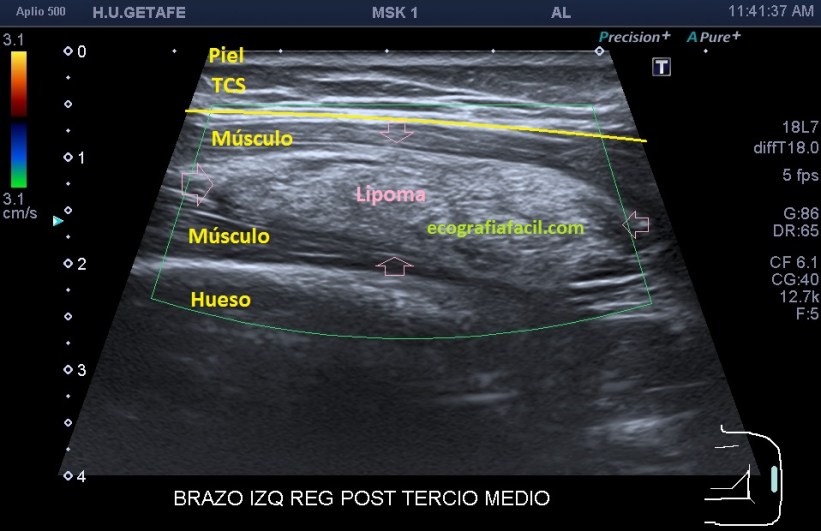

Si está por debajo, es decir, en el músculo como es en este Caso 3 que ves a continuación, la transmisión del sonido y la visualización del lipoma podrían serán peores, son los conocidos como lipomas intramusculares…mira el caso que te presento a continuación:

Como ves en este tercer caso del Post, es una mujer con un bulto en el brazo, en la localización que marcan las imágenes. El aspecto es hiperecogénico, respecto del músculo que lo envuelve que como muy bien sabes es hipoecogénico por definición. Los márgenes están marcados y definidos y el lipoma intramuscular está perfectamente localizable dentro del músculo. Su aspecto ecogénico es ligeramente heterogéneo. No tiene vascularización. Para ser un lipoma intramuscular se ve muy bien ya que está situado en una extremidad, como he mencionado anteriormente, en la cintura escapular o en paravertebrales que suelen ser habituales estos lipomas intramusculares, su visualización será un poco difícil, por la mala transmisión.

Observa la imagen 12 y 13, que son la misma, para que veas cómo se sitúa el lipoma dentro del músculo, y sus márgenes, luego para que veas la ecoanatomía de la imagen. El protocolo de estudio es el mismo siempre, localización, medición, vascularización.